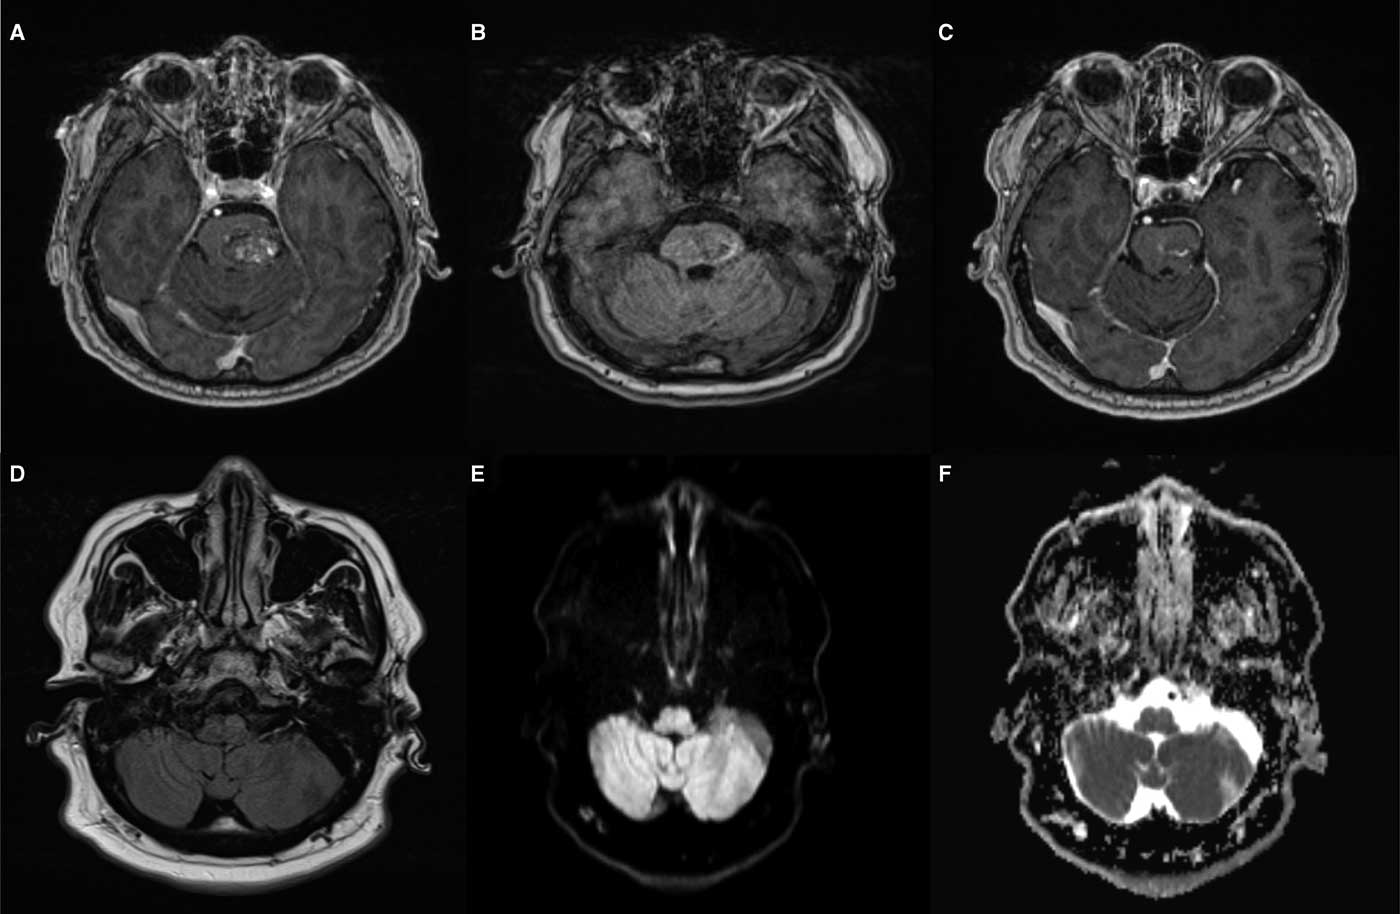

Owing to the acute onset of symptoms, computed tomography/computed tomography angiography of the head and neck was performed to rule out a brainstem stroke. The findings showed the earlier resection bed, but no acute hemorrhage or vascular occlusion. An enhanced MRI of the brain demonstrated a hypertrophied T2 hyperintense (Figure 1D) left inferior olive with no diffusion restriction (Figures 1E and 1F). A small area of T1 hyperintensity near the prior resection site suggested subacute microhemorrhage (Figure 1B).

Figure 1 Hypertrophic olivary degeneration. (A) Pre-surgical T1 post-gadolinium imaging shows a sharply demarcated heterogeneously enhancing lesion within the left hemipons consistent with a cavernous malformation. (B) T1 at the time of presentation demonstrates subtle hyperintensity along the inferolateral margin of the resection cavity consistent with subacute microhemorrhage. (C) T1 post-gadolinium at the time of presentation shows enhancing residual lesion. (D) T2 fluid attenuated inversion recovery shows hyperintensity and hypertrophy of the left inferior olivary nucleus. (E) Diffusion weighted imaging demonstrates similar subtle hyperintensity. (F) Apparent diffusion coefficient correlation also shows hyperintensity in keeping with T2 shine-through rather than diffusion restriction.

The MRI findings were specific for hypertrophic degeneration of the left inferior olive. Hypertrophy with degeneration is unique to the inferior olivary nucleus. Therefore, non-enhancing, T1 isointense, T2 hyperintense hypertrophy of the lateral medulla in the region of the inferior olivary nucleus leaves essentially only the diagnosis of HOD.